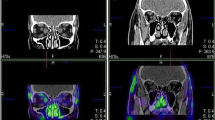

To explore the capability of 18F-FDG PET to differentiate the severity of GO patients, we compared PET parameter between the three EUGOGO severity grades (mild, moderate to severe, and sight threatening). MRI and PET images of patients with mild, severe, and unilateral GO are provided in Figs. 2, 3, and 4.

Transaxial MRI (panels A, D), PET (panels B, E), and fused slices of a 21-year-old patient with moderate, mainly left-sided GO reveal orbital tissue hypertrophy and 18F-FDG uptake, both more pronounced on the left side. The latter is more distinct on early static (panels A–C) vs. late static images (panels D–F)